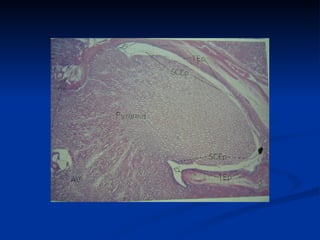

Córtex  – região externa Marrom e granular Medula  – região interna Pirâmides renais  – 6 a 12 Base orientada ao córtex – limite córtex-medular Ápice (papila renal) – orientada ao hilo. Perfurado por aberturas dos ductos de Bellini – área crivosa (semelhança a peneira). Rim

Pirâmides renais   Base  Limite córtex-medular Ápice (papila renal)  Aberturas dos ductos de Bellini – área crivosa